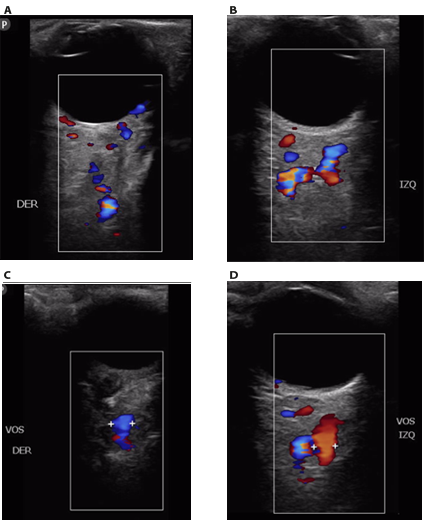

Figura 6-10. A. Ojo derecho: aumento de la vasculatura arterial y venosa de la región retrobulbar. B. Ojo izquierdo con mayor dilatación de vasos arteriales y venosos retrobulbares comparado con ojo derecho. C. Dilatación de vena oftálmica derecha de diámetro hasta 5 mm. D. Dilatación de vena oftálmica izquierda hasta 4.1 mm.